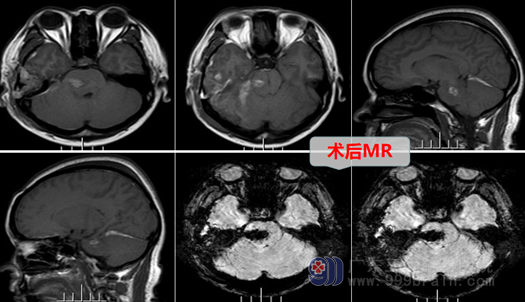

入院后欧阳辉教授带领外十科团队,为黄女士进行了进一步检查,并且开展了详细的讨论,根据检查结果及病人出血情况,欧阳主任分析:多考虑为脑血管畸形引起的脑干出血,MRI的SWI序列显象比较明确诊断为:脑干海绵状血管瘤,病变主要位于桥脑。出血的原因找到了,可问题又来了:脑干确实是生命中枢(脑)里的中枢,黄女士的病变体积直径达2.5cm,这在脑干中已经是非常大的病变了,脑干在以前被认为是生命的“禁区”,直接手术有很大的风险,在这里做手术,简直是“虎口拔牙”,那么,脑干这样的海绵状血管瘤该怎么处理呢?能保守治疗吗?面对手术风险和黄女士及家人的疑虑,外十科医生讨论后认为:手术切除病变虽然对医生是一个较大的挑战,但这是目前治疗海绵状血管瘤的最好办法,保守治疗病人的疾病不能治好,而且以后还可能反复出血,要根除这个疾病,手术治疗是唯一的选择。因此,为了病人的根本利益,欧阳辉主任团队勇于担当,决定要勇闯生命禁区,他们剑胆琴心,“明知山有虎,偏向虎山行”,首先,进行了更为详细的手术准备,为黄女士制定了缜密的手术方案,在征得病人及其家属的同意后,外十科团队于10月18日为黄女士行右侧颞下入路,脑干巨大海绵状血管瘤切除术。术中医生在显微镜放大下,抬起颞叶,用激光刀切开小脑幕,用导航精确定位脑干病变,然后雕刻式纵向切开,吸除暗红色血块,细心分离血管瘤,将海绵状血管瘤全部切除,用低温电凝精准止血。经过5小时集中精力的显微手术,终于“虎口拔牙”,成功切除了海绵状血管瘤,脑干功能并未得到损伤。

在经过五个小时的漫长等待,当李医生推着手术床上的黄女士缓缓走出手术室时,“手术非常成功”李医生对家属轻轻地说了一句,黄女士丈夫热泪盈眶,心中的一块石头终于落了地。接下来黄女士术后逐渐恢复体力,术后第三天,她惊喜的发现,自己的脚一点都不麻木了。后又经过十多天的治疗,头晕呕吐症状也消失了。此时黄女士的心中无比激动,感叹:是医生给了我第二次生命,我又可以像正常人一样生活了。出院时,黄女士丈夫送来感谢信,“致予外十科团队最高的敬意!”黄女士的丈夫在感谢信上诚挚地写道。